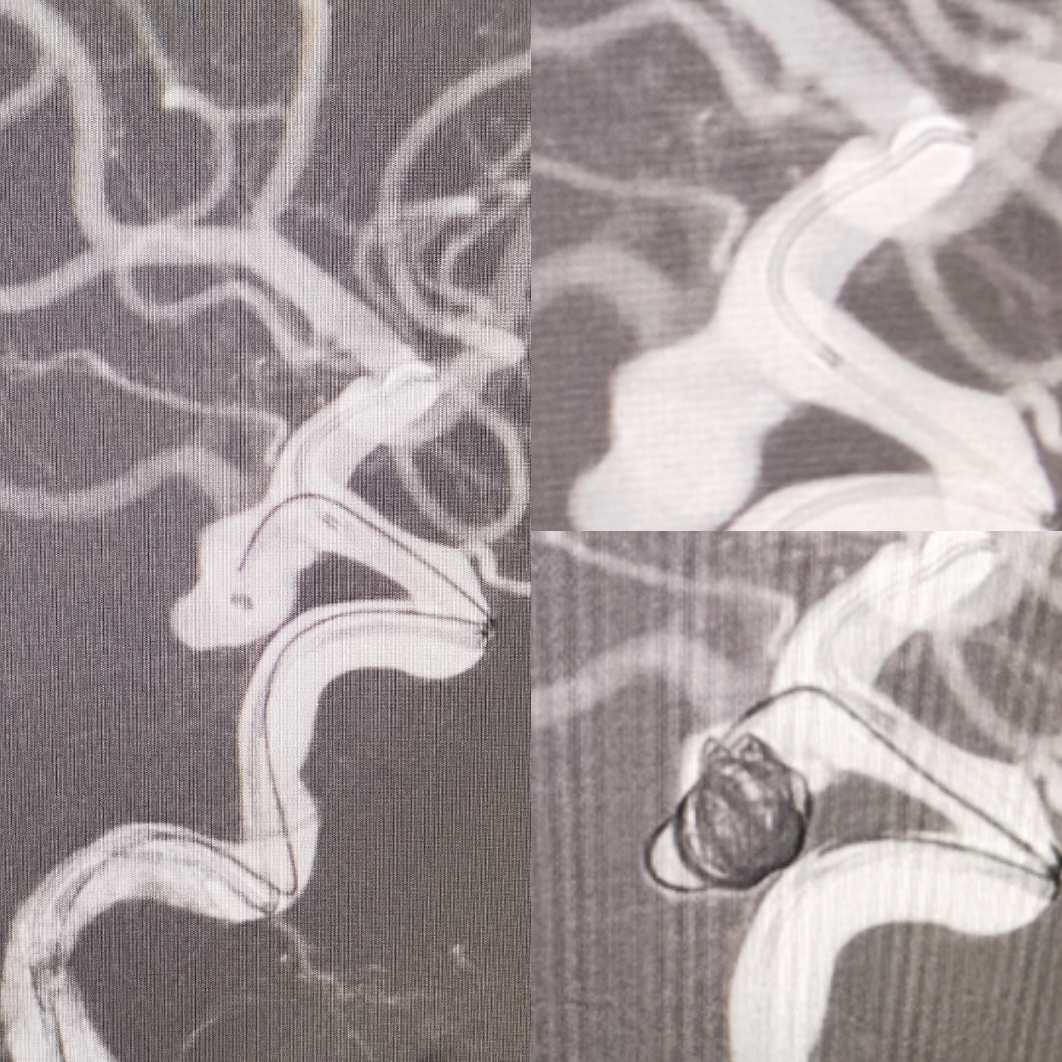

左侧椎动脉造影提示:非胚胎型大脑后动脉,有独立P1

3D旋转造影

术后3D重建

术后支架CT